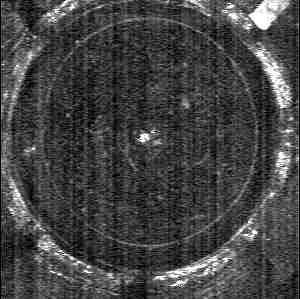

Like the natural lens, the Adaptilens A-IOL disaccommodates by flattening its anterior radius of curvature, becoming thinner, and thus reducing optical power. This video of OCT imaging from in-vitro accommodation simulations captures this dynamic behavior, demonstrating the lens transitioning seamlessly between accommodated and disaccommodated states under physiological conditions.

Top view of AIOL

Cross Section of AIOL